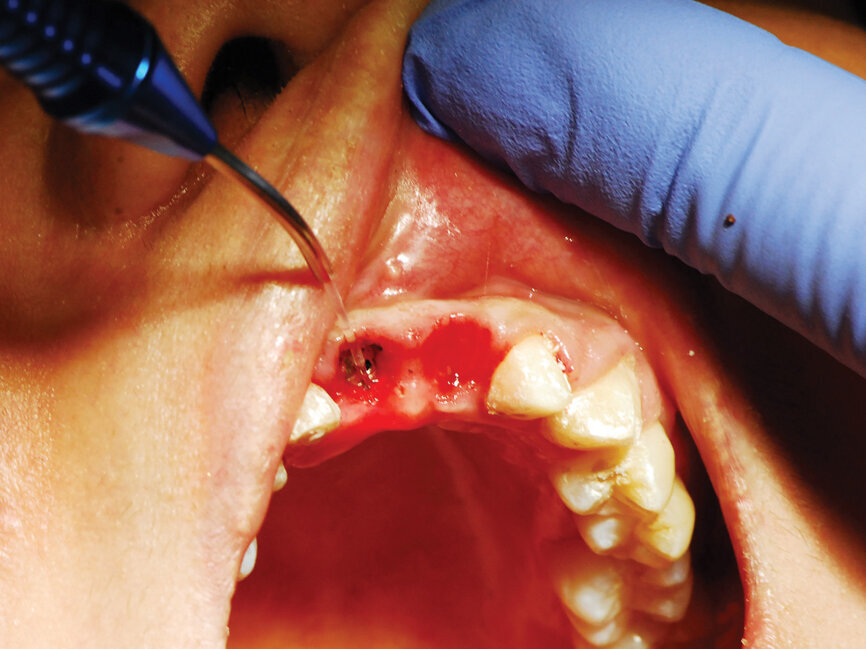

Six months post-implant placement, the provisional bridge was removed and preservation of the papillas was confirmed with a natural emergence profile within soft tissue (Figs. 6,7). Local anesthetic was administered. The Picasso Lite+ diode laser was set at 2.5 watts in continuous mode with an initiated tip and at the center of the depression in the soft tissue above the implants cover screw and moved in a circular motion moving outward until the entire cover screw was exposed (Fig. 8).

The process cuts the desired soft tissue and coagulates any bleeding from the cut edges. This was then repeated on the second implant (Fig. 9). Open tray implant impression abutments were placed into the implants and seating verified radiographically. An impression of the maxillary arch was taken utilizing Aquasil heavy body VPS (Dentsply Sirona, Milford, Del.) in a Mira Advanced Implant tray (Hager Worldwide, Hickory, N.C.) and Aquasil Ultra syringed around the preparations and implant abutment heads.